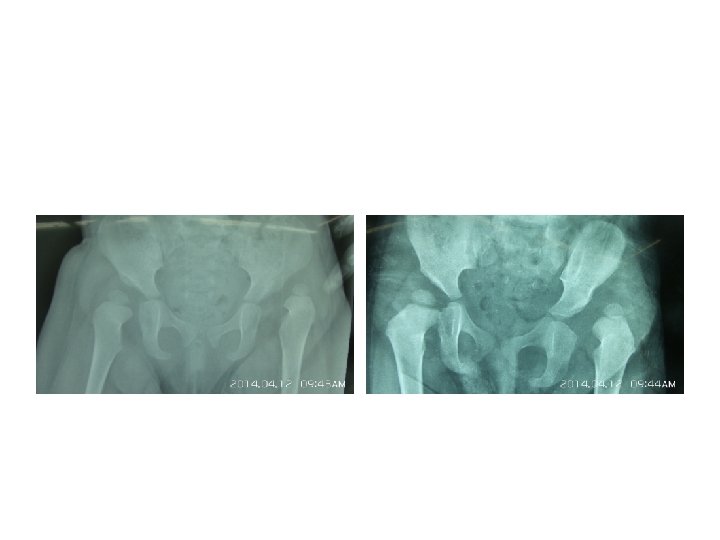

Imaging § Radiographs